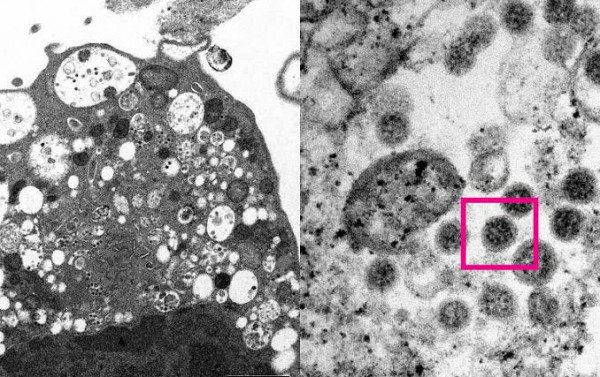

A subvariante BA.2.75 do coronavírus tem preocupado especialistas e instituições de saúde pela sua alta capacidade de transmissão. Registrada pela primeira vez em maio na Índia, ela conta com um conjunto de mutações até então nunca visto -o que pode ser uma explicação para sua disseminação.

O vírus faz parte da linhagem da ômicron, que continua sendo a variante de preocupação dominante no mundo. A BA.2.75 é uma ramificação da BA.2, uma variante da ômicron que teve seus primeiros casos no Brasil em fevereiro deste ano.

A BA.2.75 acumula uma série de mutações que ainda não tinham sido observadas. Segundo a OMS, além daquelas já registradas na BA.2, a subvariante tem oito novas mutações na proteína spike, que facilita a entrada do vírus nas células. Além destas, a BA.2.75 também tem outras cinco mutações.

É por meio da proteína spike que o coronavírus invade as células humanas. Por isso, quanto mais mutações uma variante acumular nesta proteína, as chances de maior transmissão aumentam.